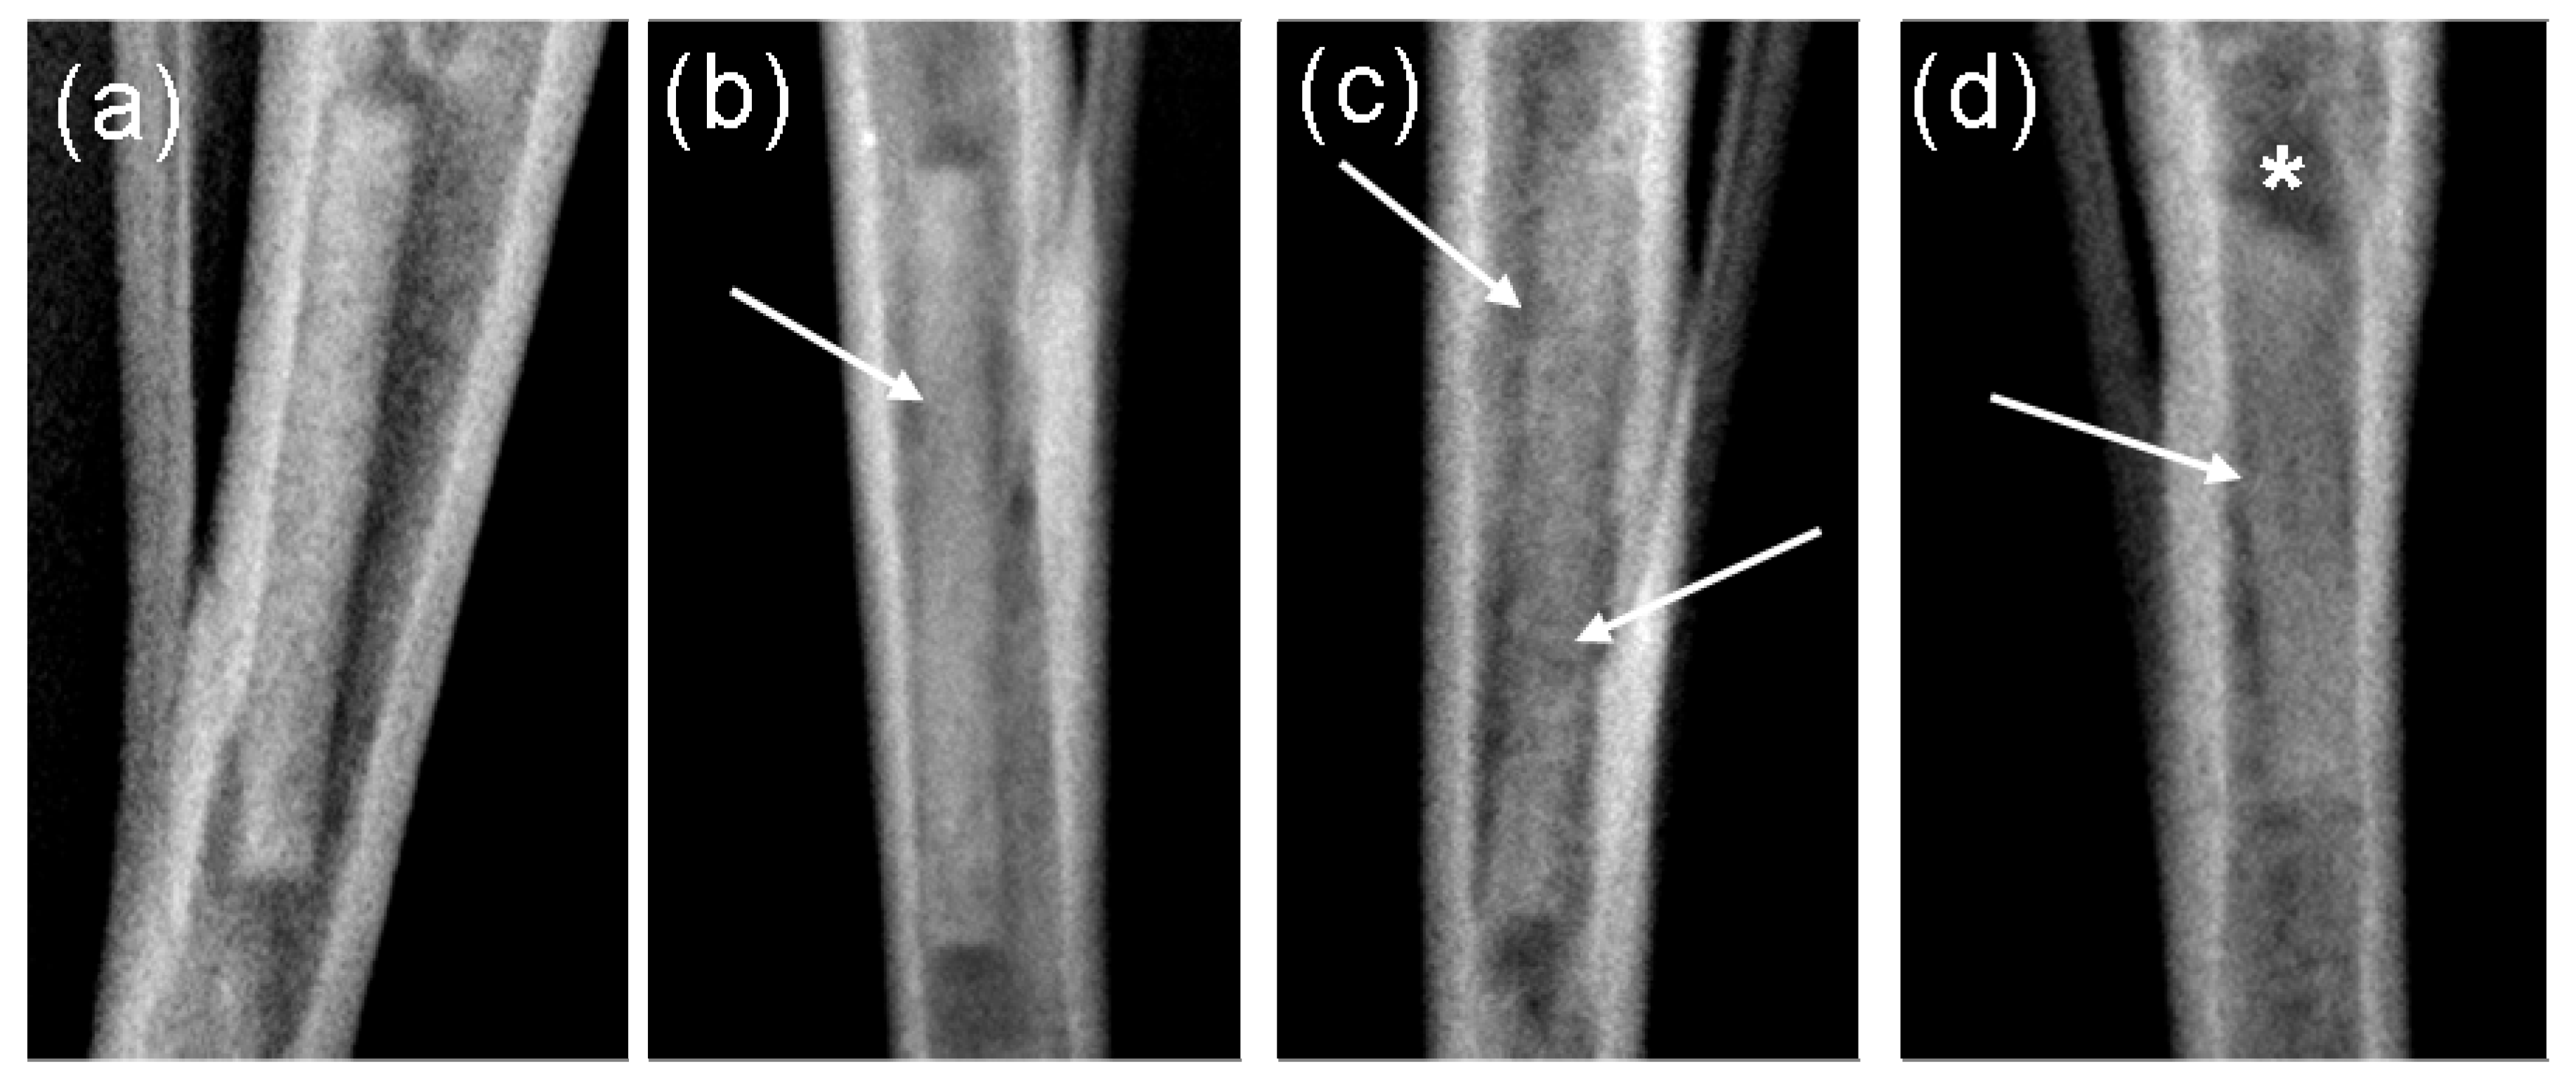

Figure 5.

Stereomicroscopy images of explanted pins (×2 magnification): (a) 4 weeks; (b) 8 weeks; (c) 13 weeks; (d) 26 weeks; each prior to (top) and following (bottom) the hydrofluoric acid treatment: The arrows indicate the more severe corrosion.

Subsequent to explantation, it was possible to observe a brown-red mass on the implants, which almost covered the entire surface. In addition to this, white crystalline-like regions were found on the surface (Figure 5). These were most pronounced in the 13 and 26 weeks groups. All the pins exhibited an almost cylindrical shape after explantation. One implant from the 26 weeks groups exhibited eroded ends, significant corrosion pitting and a shorter length in comparison to the other implants from the same group.

After the treatment in hydrofluoric acid, bright silvery surfaces possessing longitudinal grooves were discernible on all the implants. These were least formed in the 4 weeks groups. The corrosion increased with increasing implantation duration. One implant from the 8 weeks groups showed a rounded end and was more severely corroded than the remaining implants after 8 weeks. However, this did not involve the implant which was radiologically more proximally situated in the tibia. The implants of the 13 weeks groups demonstrated, on average, a more severe corrosion than the implants in the 8 week group. It was possible to discern few, very shallow cavities after 13 weeks.

In comparison to the other groups, the implants in the 26 weeks groups demonstrated the most severe corrosion. They exhibited a rough and uneven surface possessing longitudinal grooves as well as the previously described white, crystalline regions. The implants’ ends showed a tapered form and several shallow cavities on the surface (Figure 5(d) below).